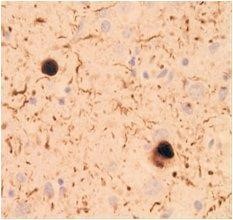

抗磷酸化α-突触核蛋白抗体

抗磷酸化α-突触核蛋白抗体是路易小体标志物,只识别累积的磷酸化α-突触核蛋白,可用于路易小体相关的病理研究。

● 已进行标记,无需使用二抗

● 低背景

● 已完成免疫染色的使用评估

路易体(即病变部位)被本产品特异性染色

数据提供:东京大学研究生院医学系研究科 岩坪老师